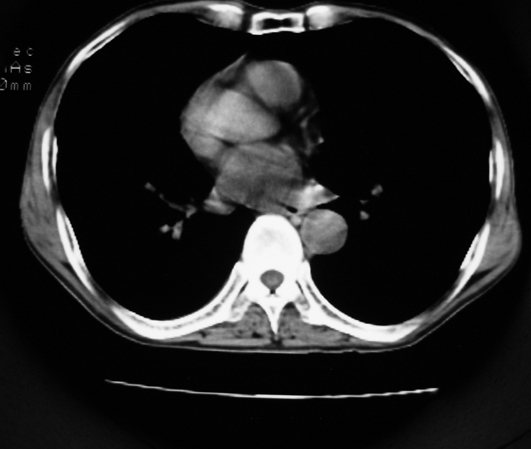

以下是引用同在2007-1-27 14:13:00的发言:[br]支持右侧中央型肺癌伴阻塞性病变.

以下是引用zjzjr在2007-1-27 16:56:00的发言:[br]支持右肺中心型肺癌伴阻塞性肺炎.